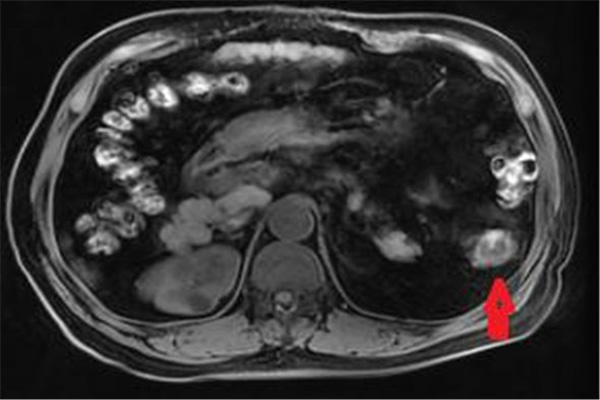

磁共振横轴位T1WI降结肠局限性增厚